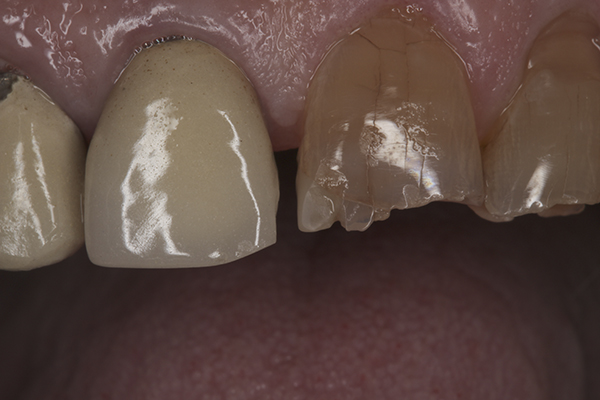

(38.) Postoperative right anterior, close-up view.

Figure 38

(39.) Postoperative anterior, close-up view.

Figure 39